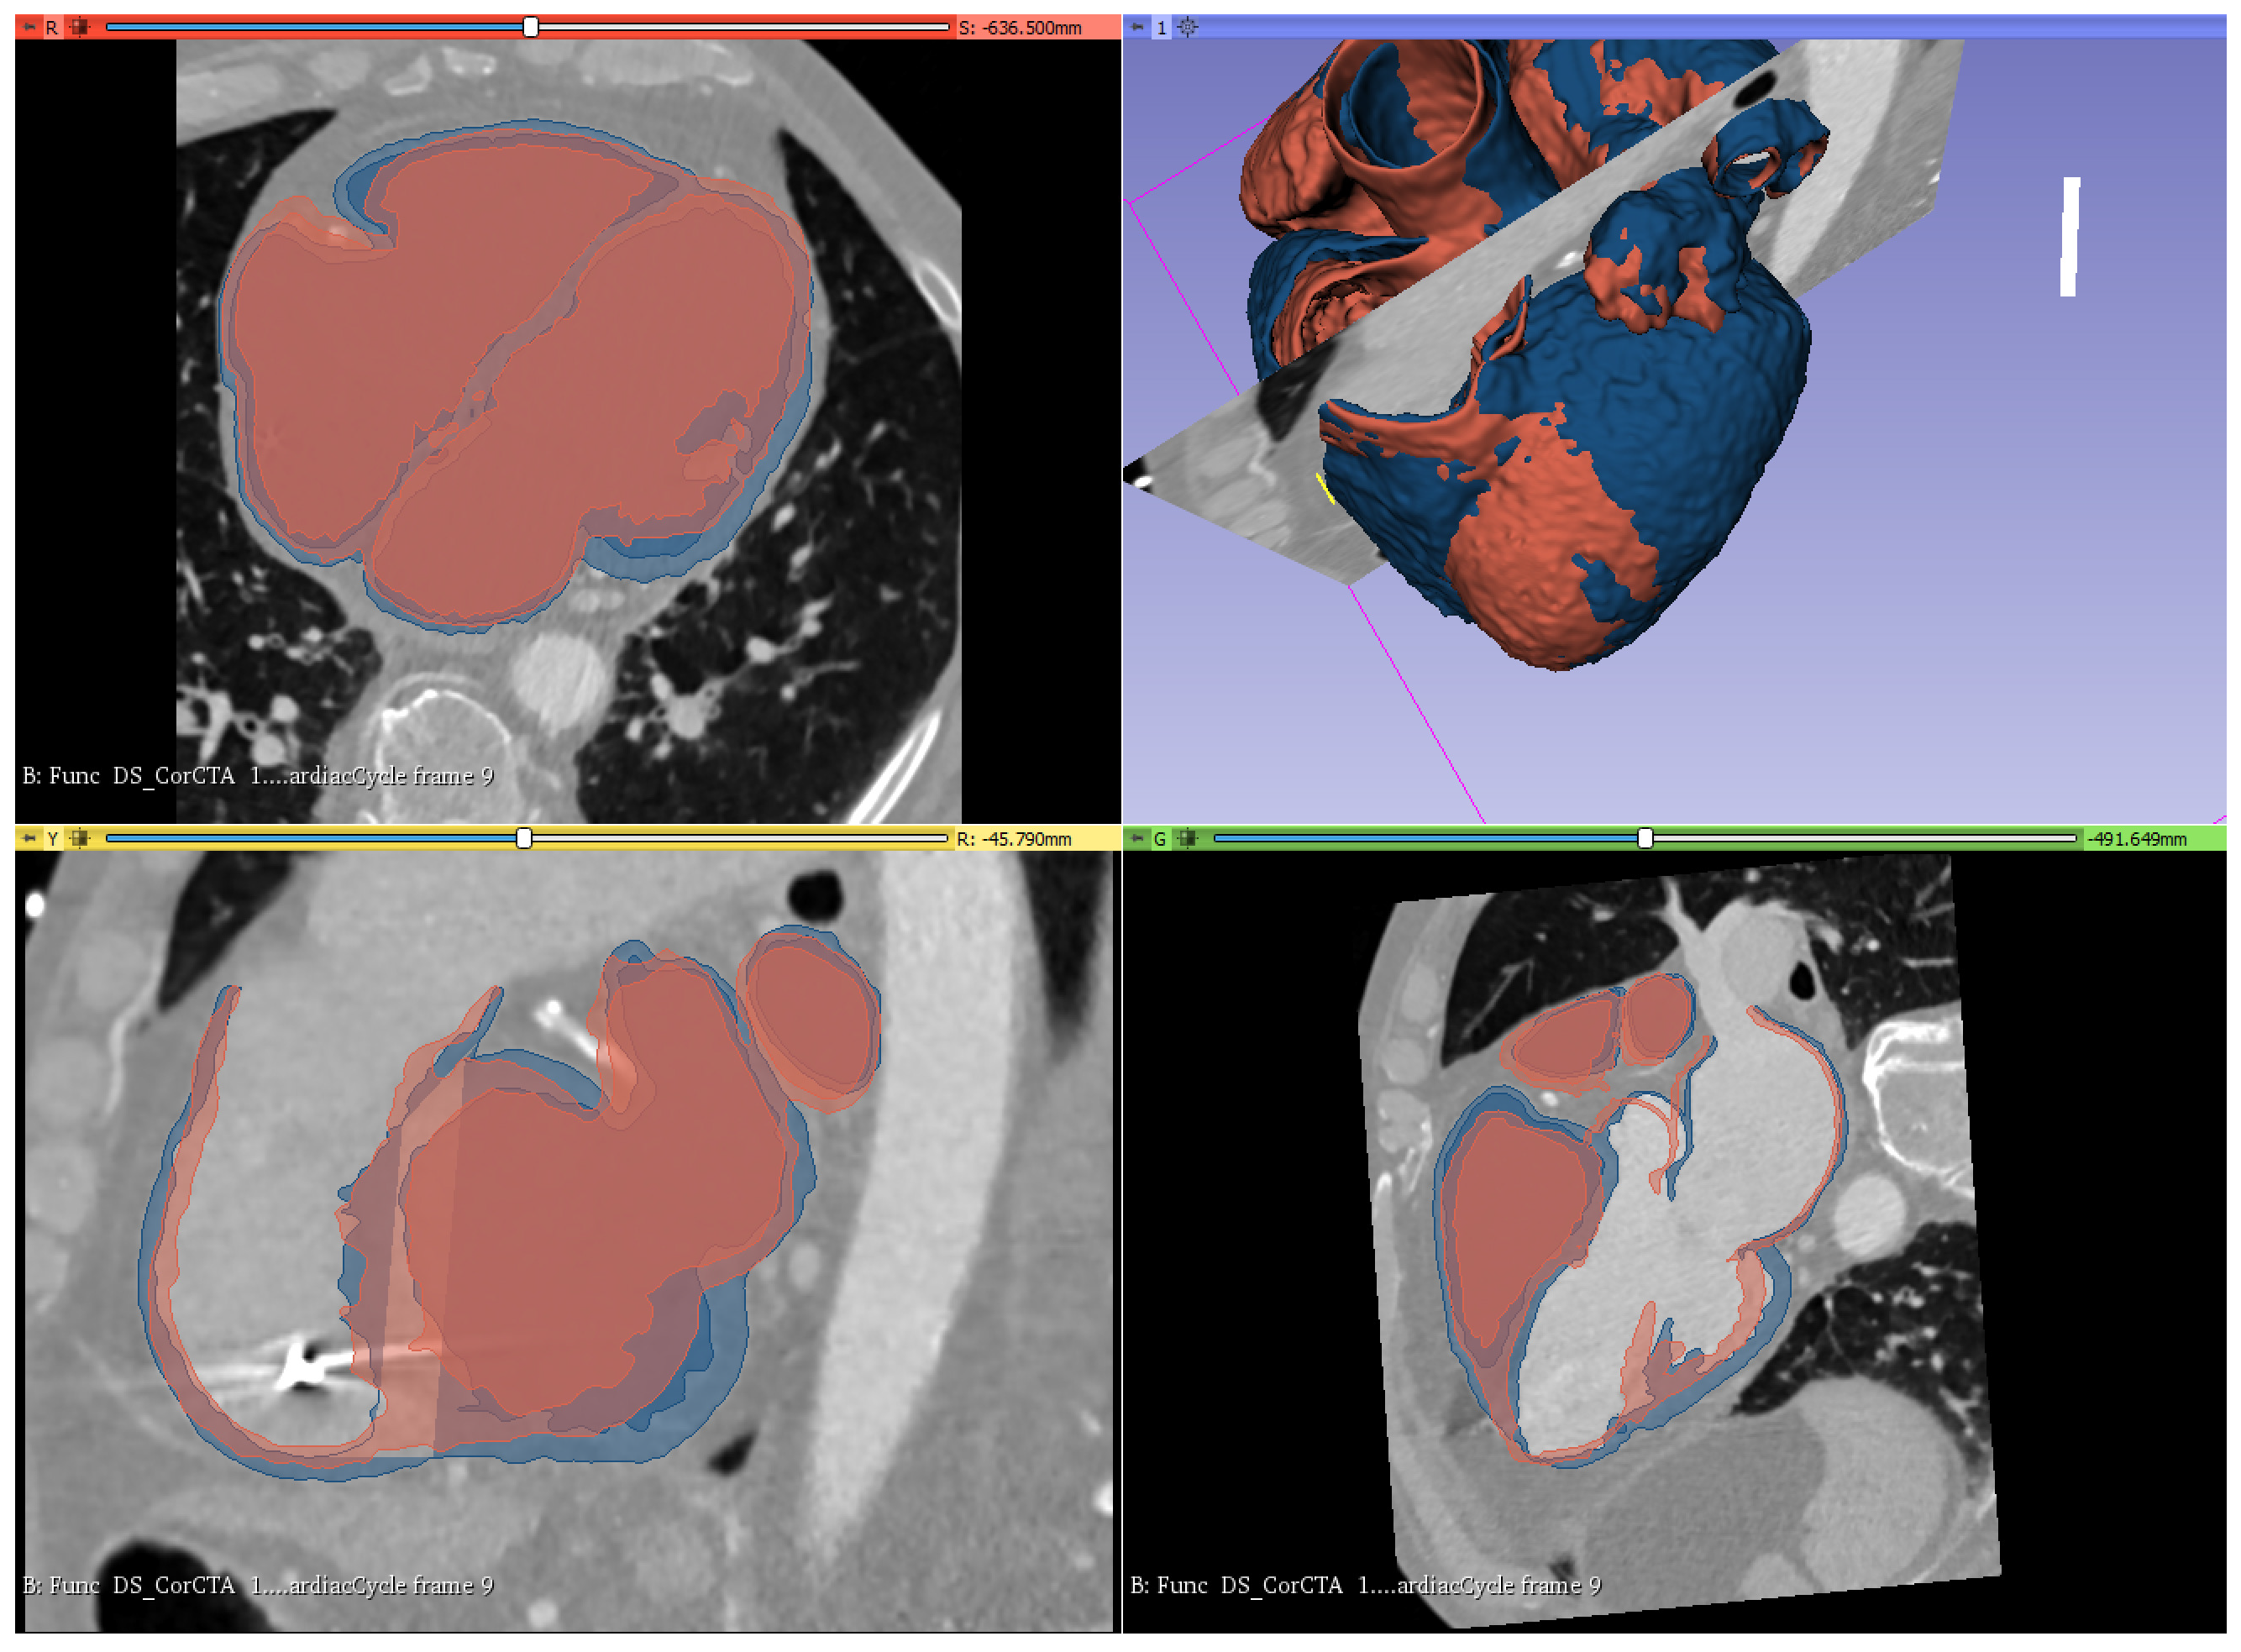

3.1. Geometry Reconstruction

- LVEF 40%—a heart muscle of very small size. It was verified that the developed ventricular balloon would cooperate in the left ventricle of this heart;

- LVEF 30%—small sized myocardium, which was the basis for the development of the ventricular balloon shape;

- LVEF 17%—heart muscle of very large size. It was verified that the developed balloon would cooperate in the left ventricle of this heart.